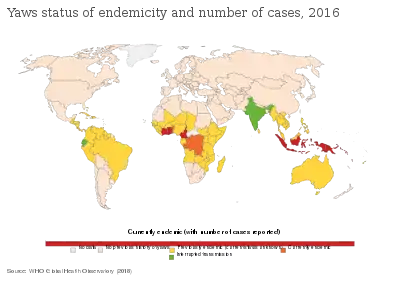

Because T. pallidum pertenue is temperature- and humidity-dependent, yaws is found in humid tropical[13] forest regions in South America, Africa, Asia and Oceania.[9][7]

About three quarters of people affected are children under 15 years of age, with the greatest incidence in children 6–10 years old.[22] Therefore, children are the main reservoir of infection.[9]

It is more common in remote areas, where access to treatment is poorer.[13] It is associated with poverty and poor sanitation facilities and personal hygiene.[9][23][7]

Worldwide, almost 85% of yaws cases are in Ghana, Papua New Guinea, and the Solomon Islands. Rates in sub-Saharan Africa are low, but tend to be concentrated in specific populations. As of 2015, it is estimated that about 89 million people live in yaws-endemic areas, but data are poor, and this is likely an over-estimate.[23]

In the early 1900s, yaws was very common; in sub-saharan Africa, it was more frequently treated than malaria, sometimes making up more than half of treatments.[9]

Mass treatment campaigns in the 1950s reduced the worldwide prevalence from 50 to 150 million to fewer than 2.5 million; however, during the 1970s there were outbreaks in South-East Asia, and there have been continued sporadic cases in South America. As of 2011, it was unclear how many people worldwide were currently infected.[24]

From 2008 to 2012, 13 countries reported over 300,000 new cases to the WHO. There was no system for certifying local elimination of yaws, and it is not known whether the lack of reports from some countries is because they stopped having yaws cases or because they stopped reporting them. It is estimated that if there is not an active surveillance programme, there is less than a 1-in-2 chance that a country will successfully report yaws cases (if it gets them) in over three-quarters of countries with a history of yaws. These countries are thought to need international assistance to mount effective surveillance.[25]

Generally, yaws is not a notifiable disease.[23]